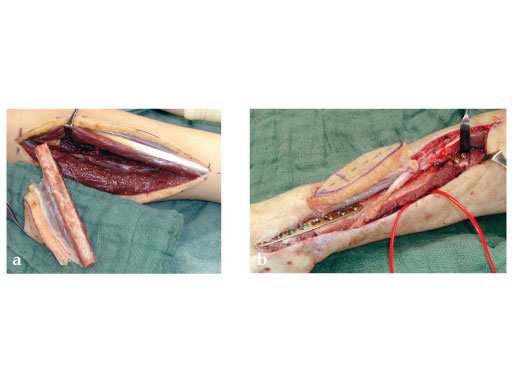

Fig 3a: Microvascular osteocutaneous free fibula flap for reconstruction of radius and dorsal skin.

Fig 3b: Proximal osteosynthesis with two screws and arthrodesis of wrist wrist with LCP 2.7.